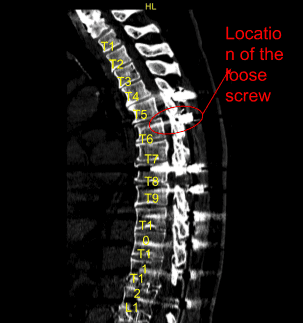

The physical examination showed tenderness of the paraspinal region at L5 on the left and right side. Fractured left-sided thoracic Z-rod with pseudoarthrosis and laterally placed proximal pedicle screw. Ct study conducted prior to the surgery supported the preoperative diagnosis of thoracic pseudoarthrosis.

Sagittal View of Preoperative CT-Scan

Next, the proximal screw on the left side at T6 was removed, which was found to be very loose, through the lateral position. Neuronavigation techniques were used to create a new trajectory for the pedicle screw more medially.